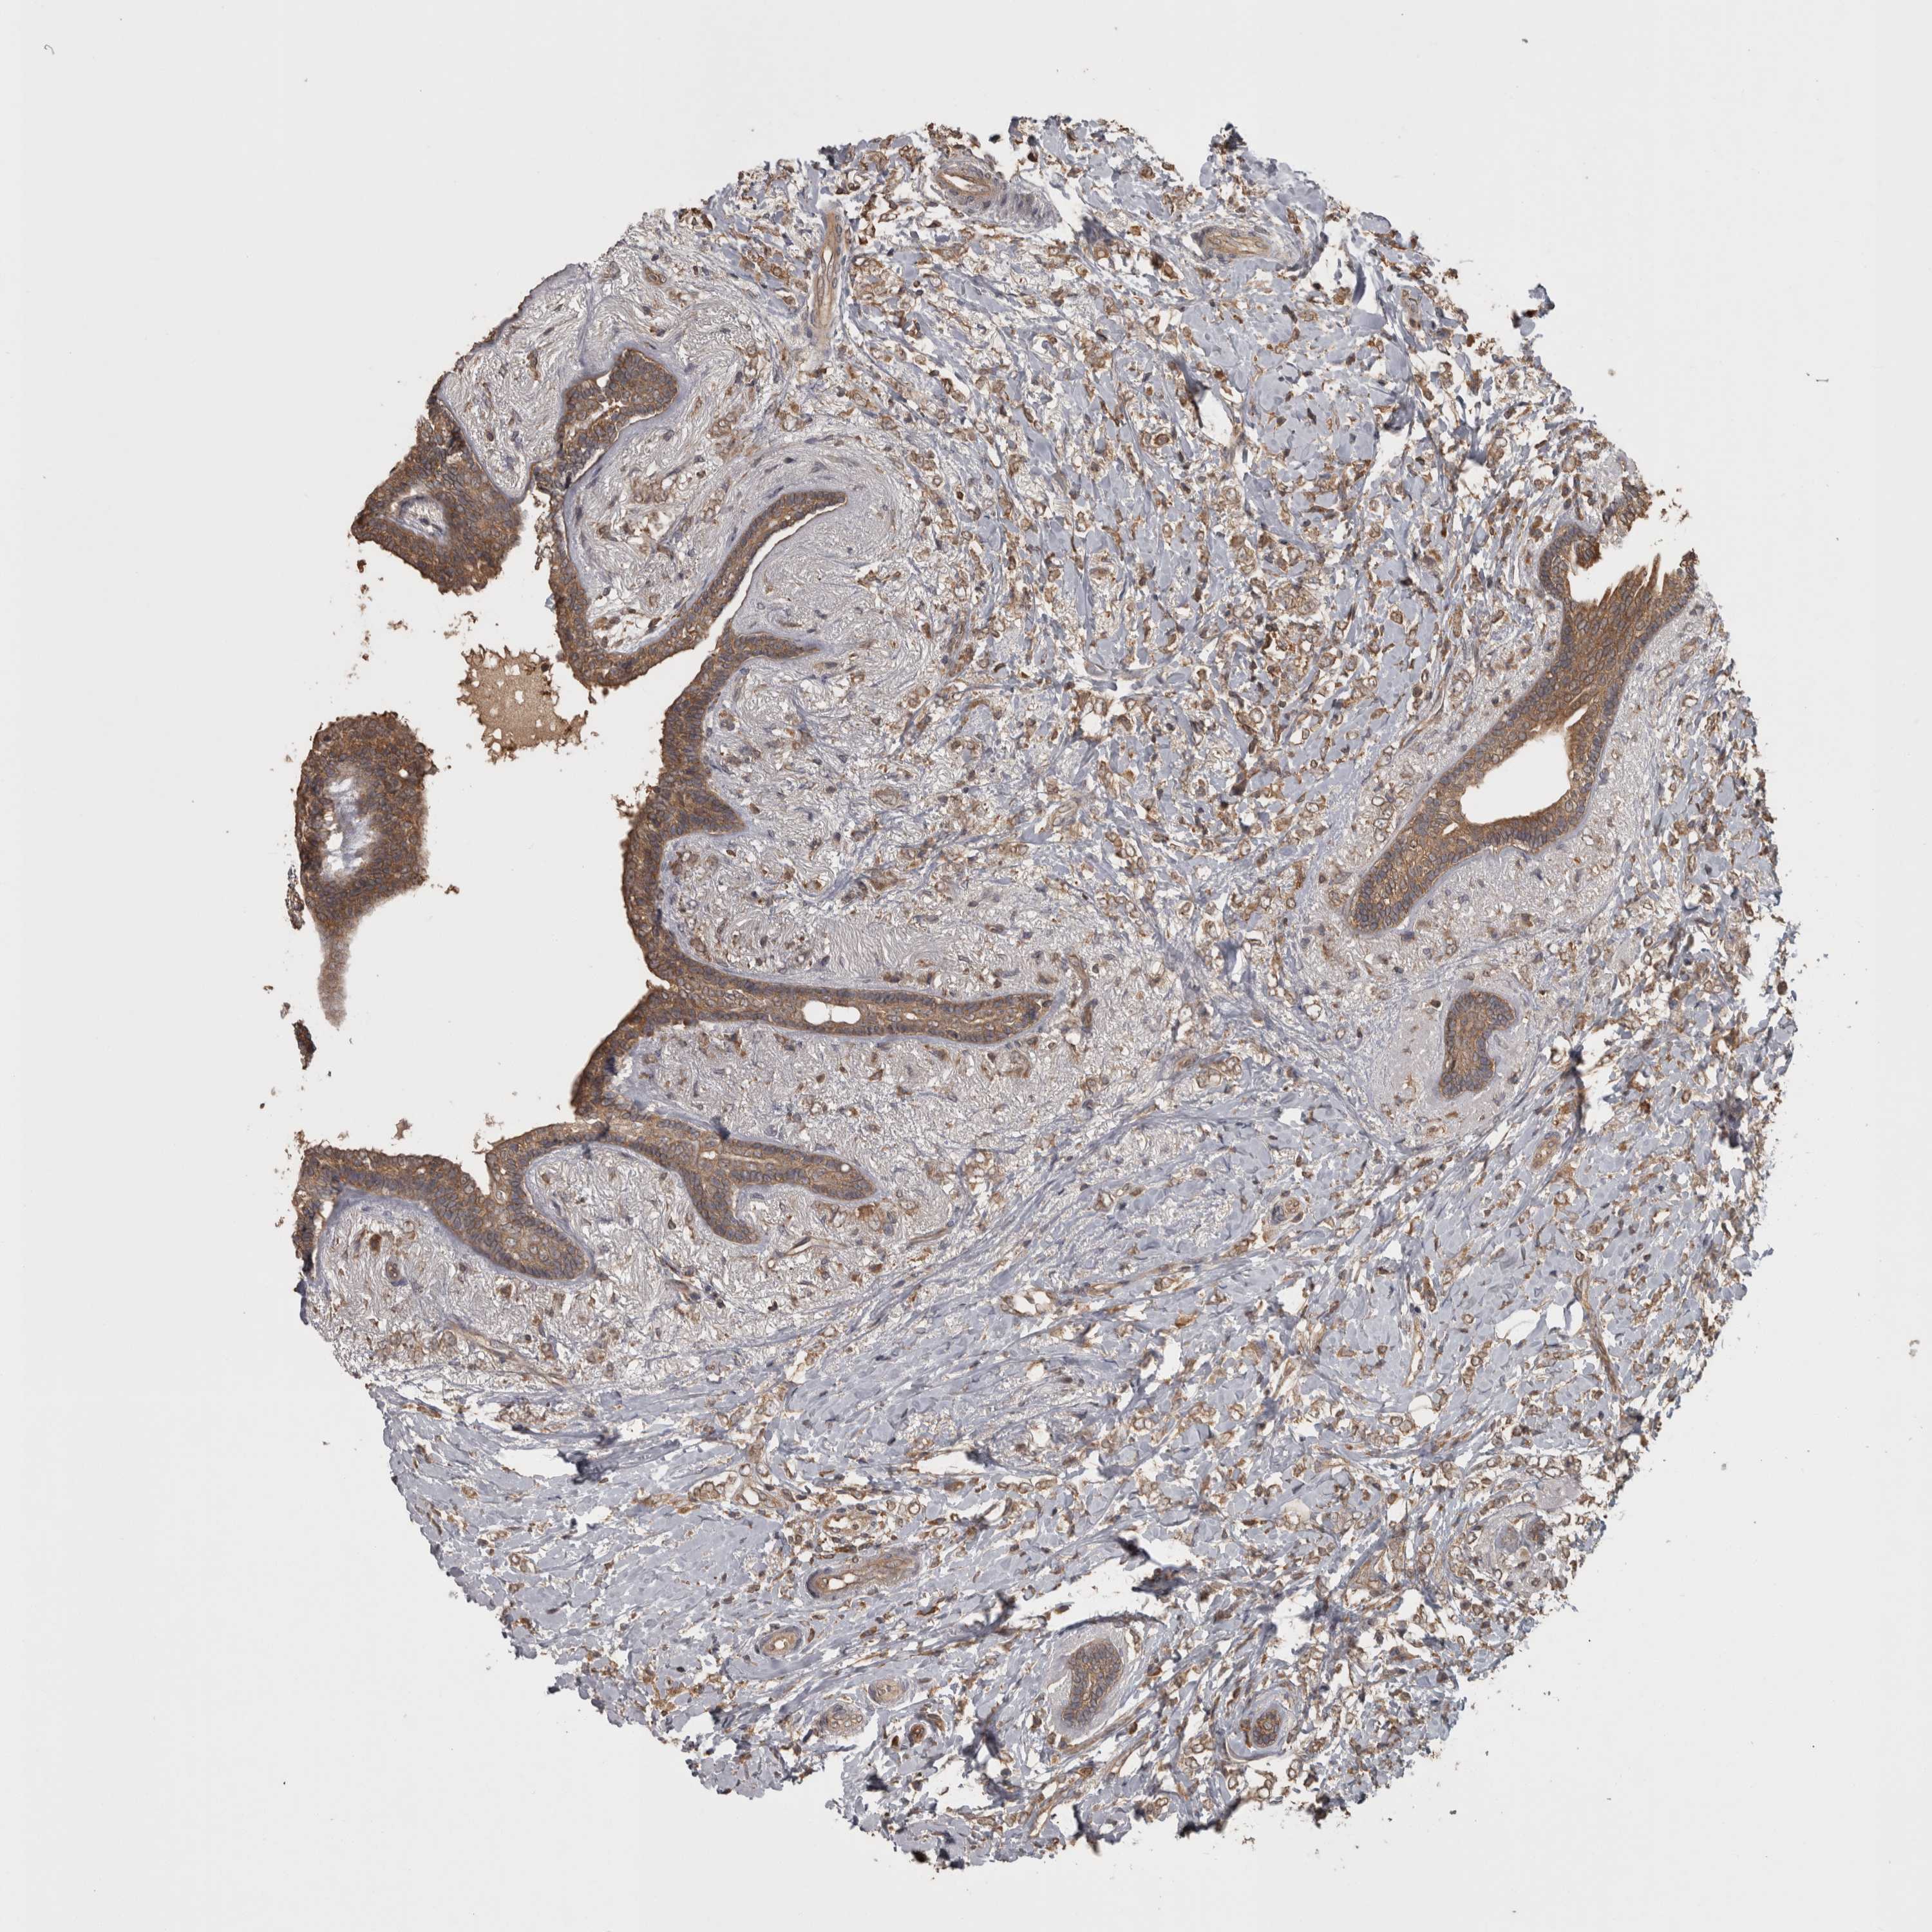

BRCA TCGA BRCA VALIDATION PROTEIN EXPRESSION

ANTIBODIES

AND

VALIDATION